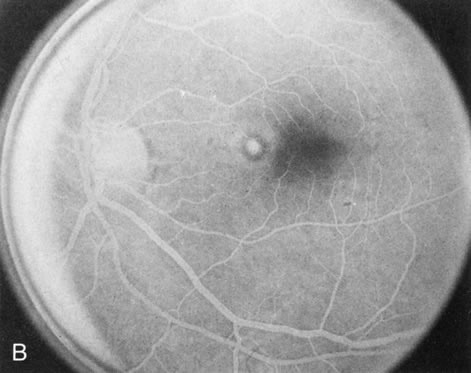

HEREDITARY HEMORRHAGIC MACULAR DYSTROPHY (PSEUDOINFLAMMATORY MACULAR DYSTROPHY OF SORSBY)

FA plays an important role in the understanding of this rare disorder. In the earliest manifestations of the disease, FA shows a single, isolated choroidal neovascular membrane unassociated with other causes of a membrane, such as drusen or angioid streaks (Fig. 13).25 Presumably this membrane is the cause of the subsequent hemorrhagic maculopathy with secondary disciform scarring, occurring initially in the macula but often extending throughout the retina.

Fig. 13. Hereditary hemorrhagic macular dystrophy (pseudoinflammatory macular dystrophy of Sorsby). Fluorescein angiography in this family member demonstrates that the earliest finding is an isolated choroidal neovascular membrane B). Despite laser photocoagulation, a hemorrhagic maculopathy developed in this eye (C, D) and eventually a disciform scar (E) formed, as it had in the fellow eye, and in the eyes of other affected family members.

Abnormal choroidal perfusion, manifested on FA as a delay in choriocapillaris filling, has been seen in the restudy of some of Sorsby's initial pedigrees.26 This unusual pattern has been related to the histopathologic finding of a “confluent, lipid-containing, amorphous deposit found between the basement membrane of the RPE and the inner collagenous layer of Bruch's membrane.”27